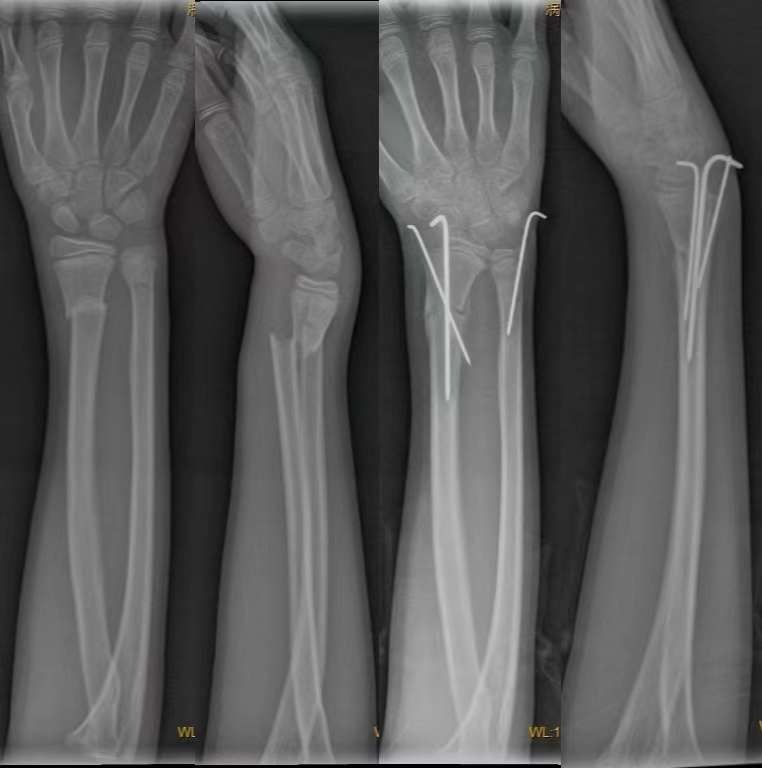

桡骨远端骨折(Distal radial fractures)---是指距桡骨远端关节面3cm以内的骨折,是松质骨和密质骨的交界处,横截面呈四边形且骨皮质较弱因此力学结构较弱,骨折后容易发生松质骨的塌陷,皮质骨的粉碎及桡骨缩短现象。

2.经皮穿针固定:具有手术简单、取出容易、较少影响肌腱功能等特点。适应征:既可以作为一种单独的外固定方法,也可以作为石膏外固定和外固定架的有效辅助措施。单独应用时,适用于关节外骨折,闭合复位后早期出现再移位的骨折,以及一些能闭合复位但无法靠外固定维持位置的关节内骨折。年龄<65岁的关节外骨折、伴有干骺端轻微粉碎的骨折或无移位的关节内骨折。